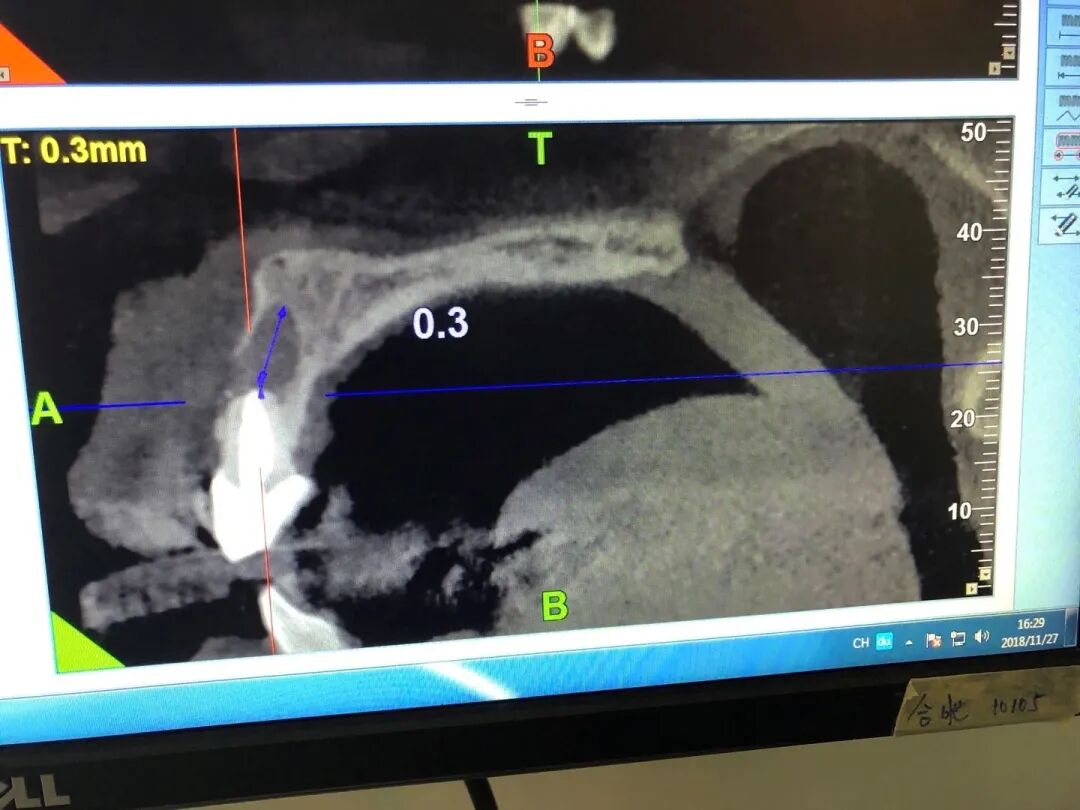

根尖囊肿CT侧视图

蓝色斜线处就是,可以看到已经侵占了正面的牙槽骨孔

| 作者供图